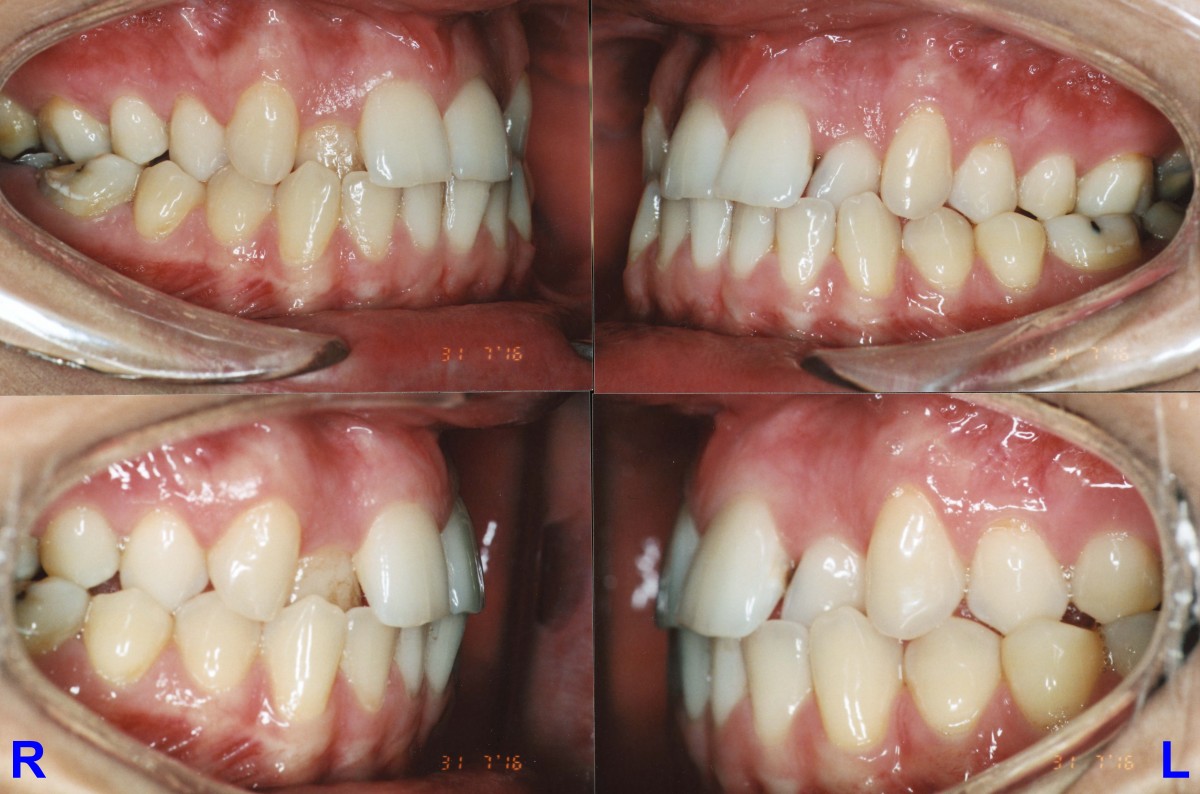

Pacient, 26 ani. Caz nonextracționist, Expander Maxilar + aparate ortodontice fixe bimaxilare.